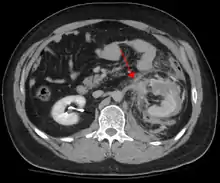

الصدمة البطنية الحادة تضم 75٪ من كل صدمة حادة وهي أكثر الاصابات شيوعاَ وأسبابها غالبا تكون من حوادث السيارات عندما يحدث تباطؤ سريع قد يدفع السائق للمقود أو للوحة عداد السيارة أو حزام الأمان مما يسبب كدمات في الحالات الأقل خطورة أو تمزق بالأعضاء الداخلية بارتفاع بسيط بالضغط في الحالات الأكثر خطورة اعتمادا على القوة المطبقة. هناك آليتين فيزيائيتين أساسيتين تلعب في احتمالية اصابة الأعضاء البطنية الداخلية هما: الضغط والتباطؤ يحدث الضغط بسبب الضرب المباشر كاللكمة مثلًا أو الضغط على جسم غير مرن كحزام الأمان أو عامود التوجيه وهذه القوة قد تتسبب في تشويه عضو مجوف وبالتالي سيزداد الضغط داخليًا فسيؤدي إلى حدوث تمزق, ومن ناحية أخرى، قد يسبب التباطؤ تمدد أو قطع في الهياكل الناقلة عندما ترتكز كالأمعاء ويتسبب ذلك بتمزق مساريق الأمعاء وإصابة الأوعية الدموية التي تنقل داخل هذه المساريق. ومن الأمثلة الكلاسيكية لهذه الآليات: التمزق الكبدي على طول الرباط المدور واصابة الشرايين الكلوية. عندما تتعقد الإصابات البطنية الحادة بالإصابات الداخلية، فالكبد والطحال (انظر إلى صدمة كليلة في الطحال) قد تتأثر في معظم الأحيان تليها الأمعاء الدقيقة.

تقريبًا بالإصابات البسيطة الأكثر وضوحًا، الشأن الأول هو استبعاد أي شيء قد يكون مهدد للحياة بشكل مباشر و صريح ويتم حل ذلك عن طريق التأكد من أن مجرى الهواء مفتوح بشكلٍ كاف وذلك بأن يكون التنفس طبيعي بلا مشقة مع امكانية الإحساس بنبضات الدورة الدموية ويوصف ذلك أحيانًا بثلاث نقاط (أ،ب، ج) أي مجرى الهواء والتنفس والدورة الدموية، وهذه هي الخطوة الأولى في أي إنعاش بعد ذلك تاريخ وقوع الحادث أو الإصابة يؤخذ بشكل طبي وغذائي ( توقيت آخر تناول عن طريق الفم) والتاريخ السابق يؤخذ من عائلته أو أصدقائه أو حتى معالجيه السابقين وهذه الطريقة في بعض الأحيان تعطي عينة تذكيرية كما وينبغي أن لا يكون الوقت المستنفذ في عملية التشخيص طويلًا والإسراع من قبل مجموعة من التقييم السريري والاستخدام الملائم للتكنولوجيا مثل تشخيص الغسيل البريتوني (DPL) أو الفحص السريري للموجات الفوق صوتية (FAST) قبل الشروع في البطن إذا لزم الأمر فإذا كان الوقت واستقرار حالة المريض مأذون بهما فيمكن إجراء فحص تصوير مقطعي إذا كان متاحًا وتشمل مزاياه تعريف متفوق من الإصابة مما يؤدي إلى درجات الإصابة وأحيانًا الثقة لتجنب أو تأجيل الجراحة ومن سلبياته الوقت المستغرق للحصول على الصور على الرغم من أن هذا الوقت يقل مع كل جيل من الماسحات الضوئيّة وإزالة المريض من وجهة النظر المباشرة لموظفي الطوارئ أو موظفين الجراحة. مؤخرًا تم تحديد المعايير التي قد تسمح للمرضى المعانين من الصدمات الحادة في منطقة البطن ليتم معالجتها بشكل آمن دون المزيد من التقييم، و من خصائص هؤلاء المرضى ما يلي: